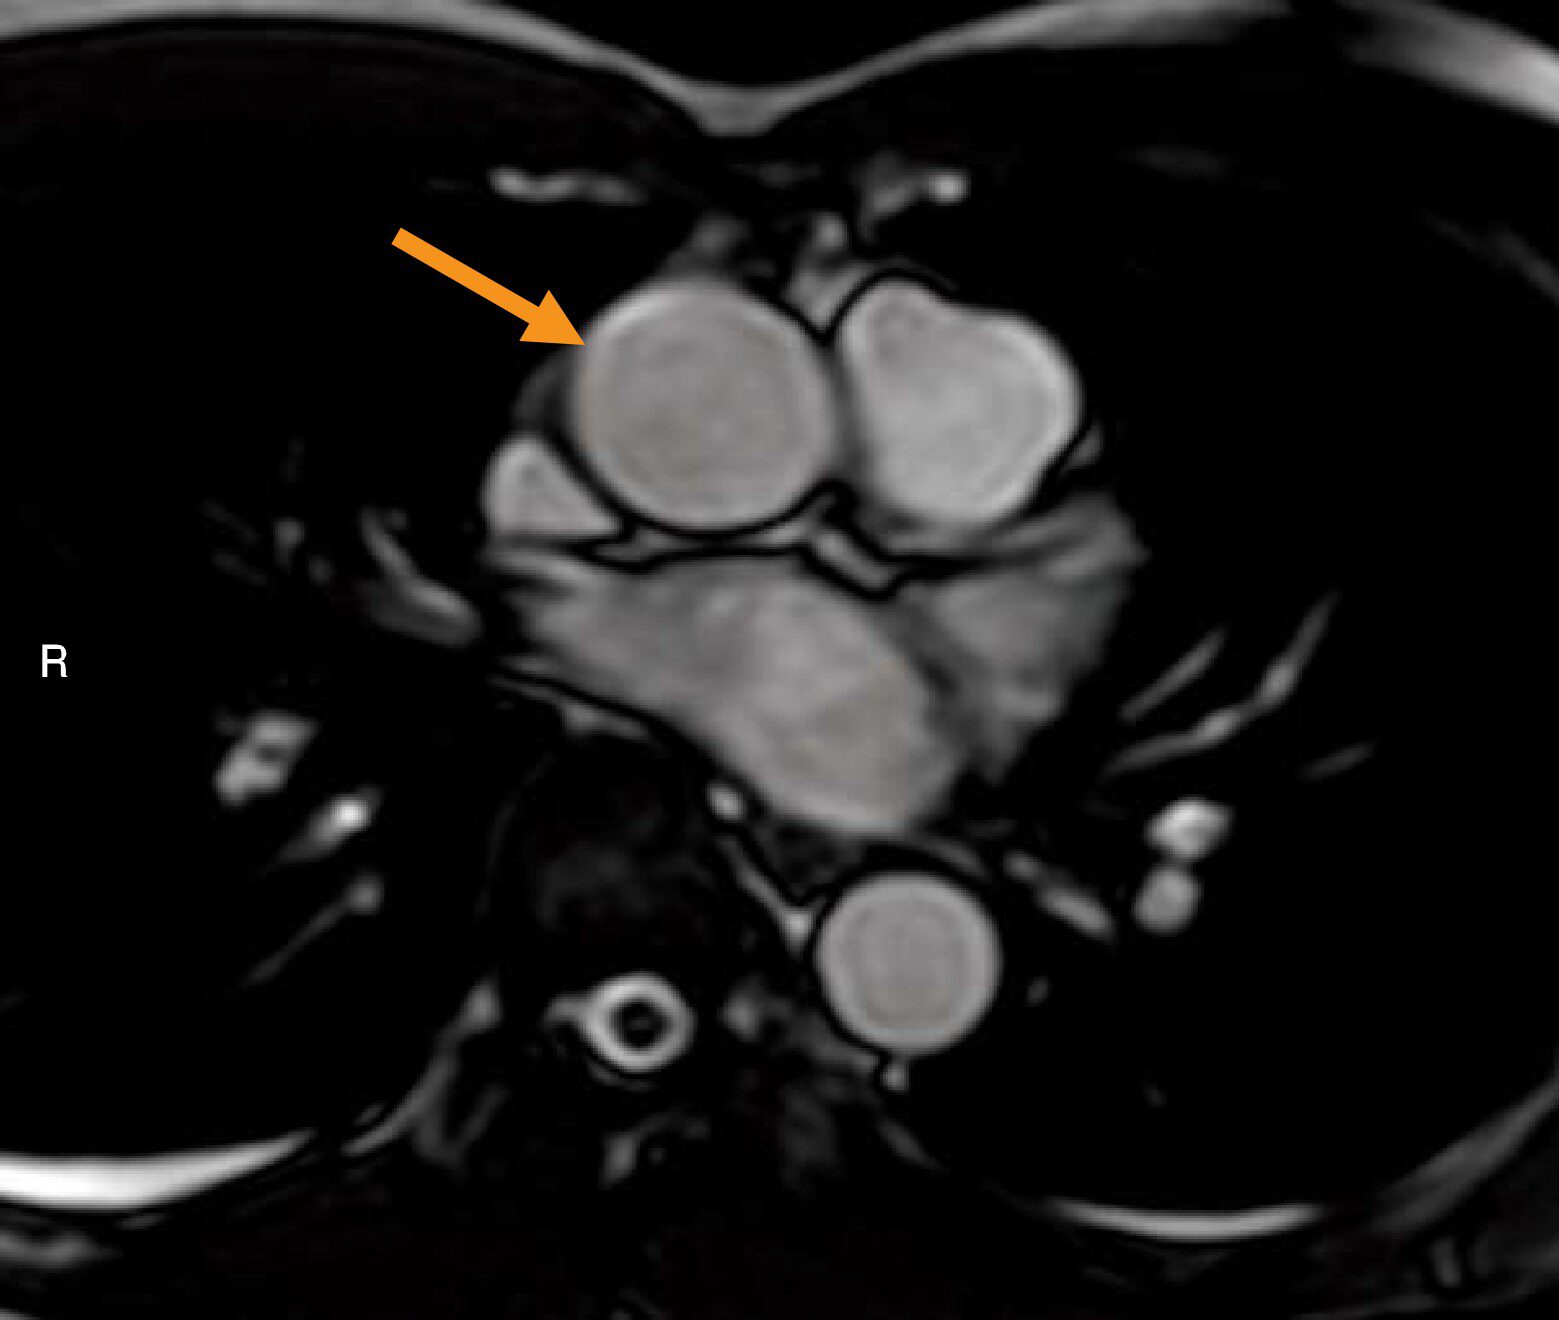

Q9 / 20医用画像撮影技術学

胸部MR像(別冊No.4)を別に示す。矢印で示す血管と直接交通しているのはどれか。

- 1右心房

- 2右心室

- 3左心房

- 4左心室

- 5下大静脈